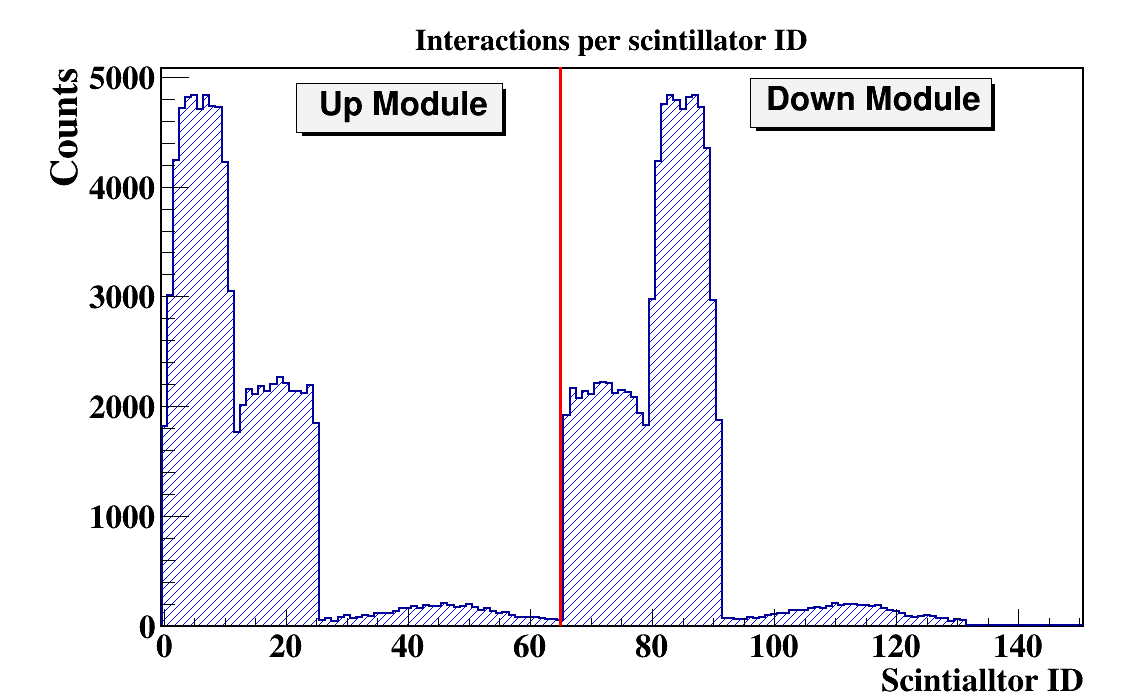

In order to quantify the J-PEM geometry we have performed Monte-Carlo simulations. The simulations were performed using the GATE package. GATE (Geant4 Application for Tomographic Emission) is a Monte Carlo simulation platform developed by the Open-GATE collaboration [40] based on Geant4 software. It is dedicated to numerical simulations in medical imaging and radiotherapy. It utilizes an easy macro mechanism to configure the experimental settings for computed tomography, single photon emission computed tomography, positron emission tomography as well as optical imaging (bioluminescence and fluorescence) or radiotherapy. In the simulations the full geometry of the J-PEM detector and the composition of the detector material were taken into account. The interactions of photons in the scintillators were simulated by GATE. In the simulations we assumed that annihilation source is placed in the center of the detector and that the back-to-back photons (each with energy of 511 keV) from the Ps annihilation are isotropically emitted. Energy deposition inside the plastic scintillator is shown in Fig.7. According to the performed simulation we are able to register 4.33% of generated back to back events. After adding the condition that both photons deposited at least 200 keV energy fraction of register annihilation drop to 0.8 % . Such a condition is needed for the suppression of the scatter fraction [41]. We found that there was 11.3% primary back-to-back registered events where at least one photon scattered in WLS.